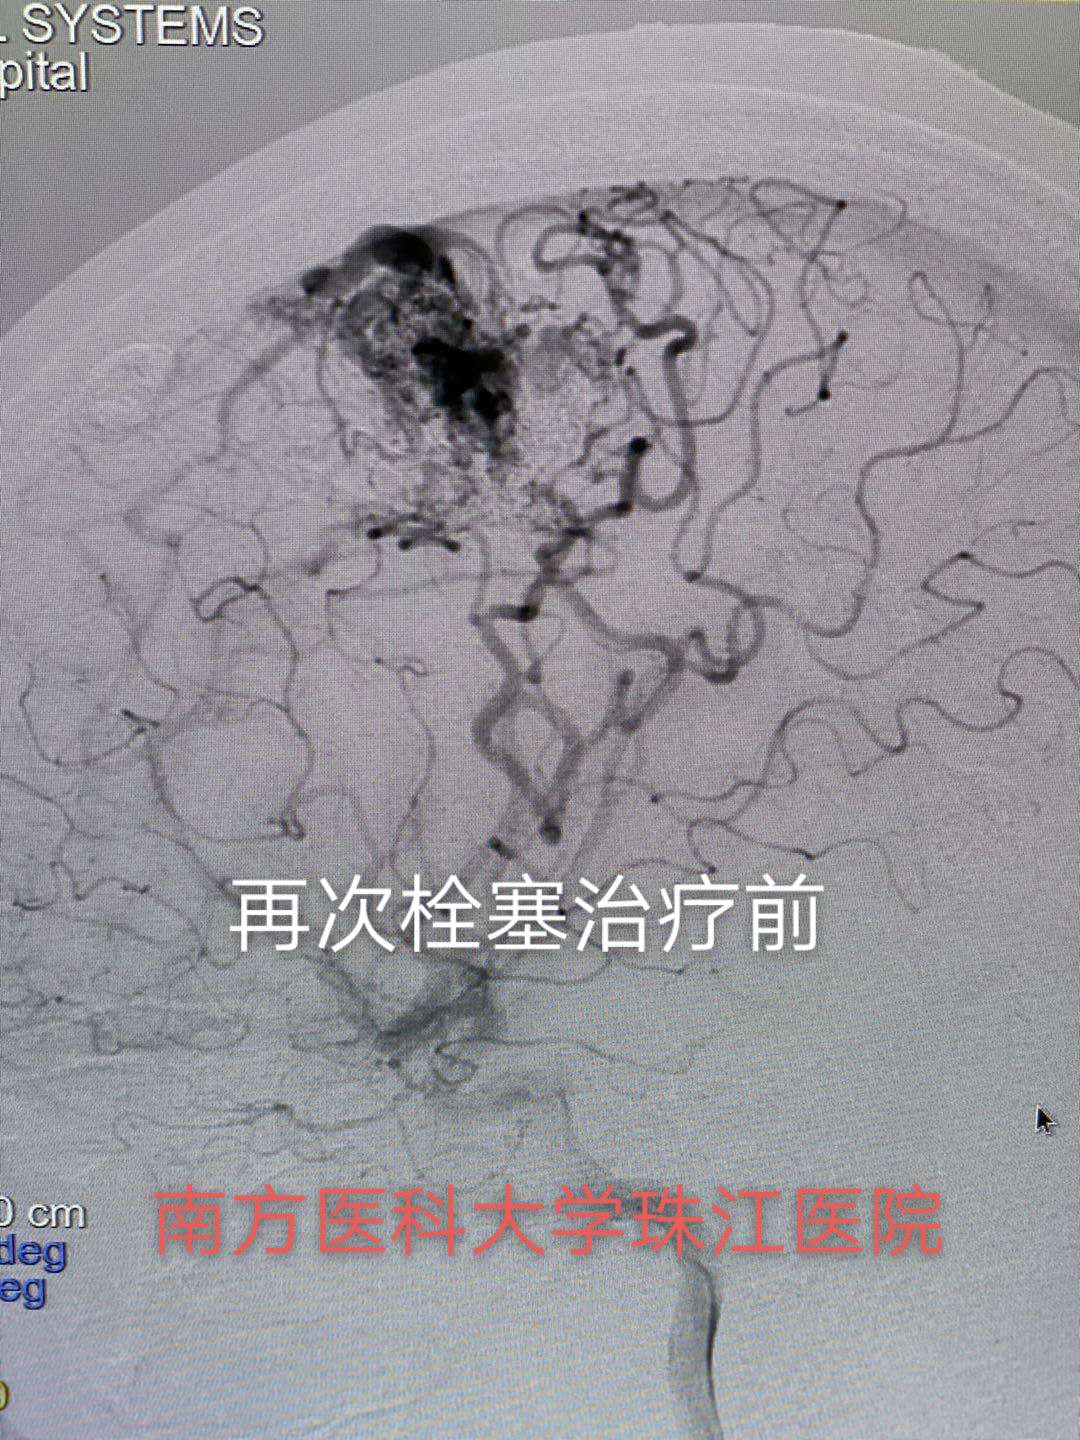

病例2 静脉入路

大多数情况下,通过介入治疗可以达到完全治愈的目的,针对部分患者血管内栓塞治疗是手术切除或放射外科治疗前的有效辅助治疗办法,通过一次或数次栓塞治疗将畸形团变小、栓塞其中的伴发动脉瘤、高流量动静脉瘘等,为手术、放射外科治疗创造条件。